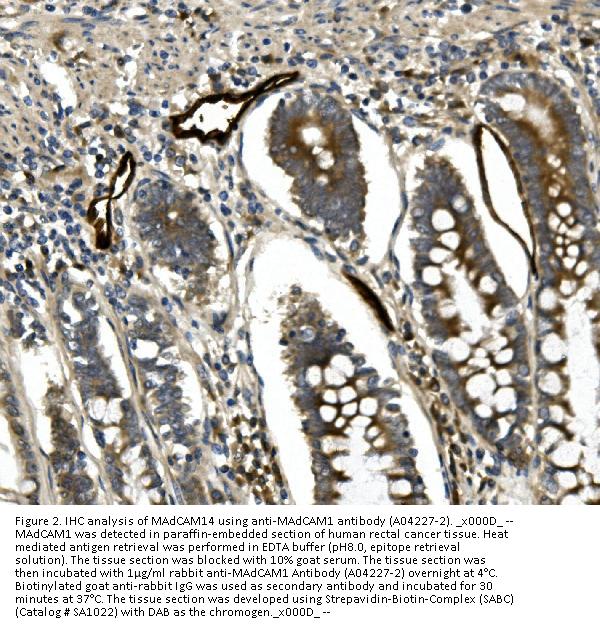

Immunohistochemistry (Paraffin-embedded Section), 0.5-1μg/ml, Human

Boster Bio Anti-MAdCAM1 Antibody Picoband® catalog # A04227-2. Tested in IHC applications. This antibody reacts with Human.